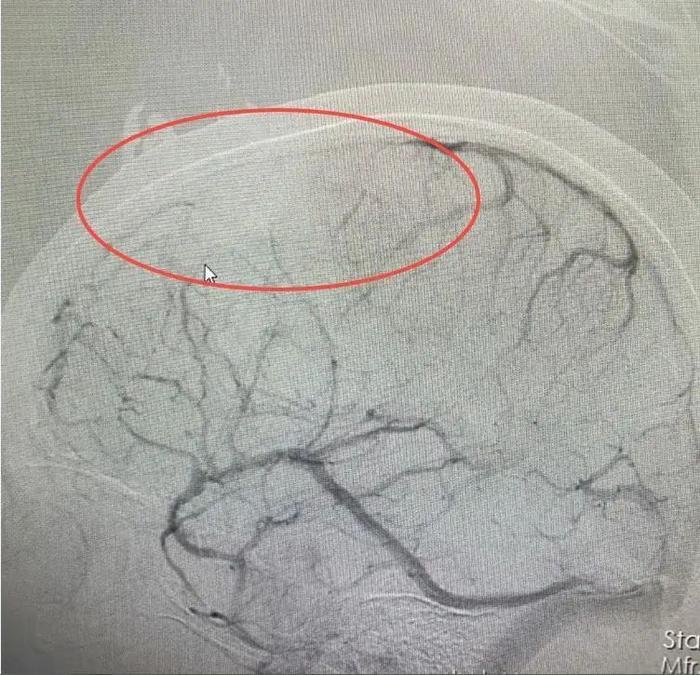

医院接诊医生仔细分析后,发现婷婷颅内病变不是脑肿瘤。结合病史和相关影像资料,该院神经内一科副主任匡祖颖初步怀疑是颅内静脉窦血栓。进一步完善全脑血管造影,证实是颅内静脉窦血栓形成合并出血。

全脑血管造影检查

据了解,颅内静脉窦血栓与血管病变、血液成分改变以及不良生活习惯和过度疲劳等有关。该院副院长、神经内科专家王展航解析:“患者原本就贫血,不科学的减肥方法加重了贫血,加之长期熬夜,饮食、作息极不规律,导致血液处于高凝状态,这是静脉窦血栓形成的主要因素。”